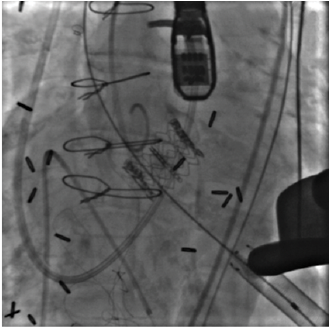

Editor’s Note: Originally published by the Journal of Invasive Cardiology in 2014 and republished in the March 2024 issue in honor of Dr. Alain Cribier, this case by Kernis et al describes one of the thousands of transcatheter aortic valve replacement (TAVR) patients benefiting from Dr. Cribier, a pioneer of the TAVR procedure.